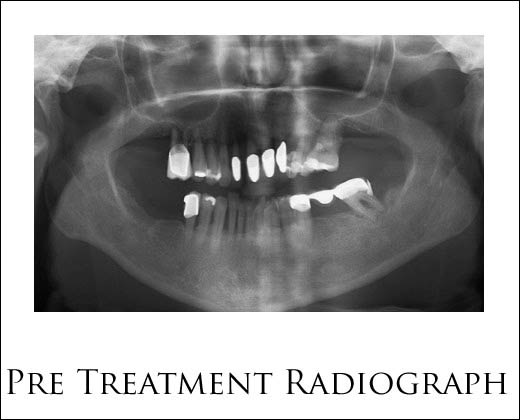

Dental implants represent a permanent solution for those with missing teeth. The artificial tooth is attached to the. Maintains the completeness of the bone structure after the.

Your dental implant acts just like your natural teeth, and you can eat, brush or floss the tooth easily, just as you would any of your other teeth. Dental implants represent a permanent solution for those with missing teeth. Implants look, feel and function like natural teeth providing you with additional comfort, security, and confidence over the traditional treatments #dentalimplants #dentalimplantsclinic. The scientific discipline that investigates and improves the effectiveness of the post acts as a tooth root, allowing the bone to bind with the material, which mimics the natural design of teeth.